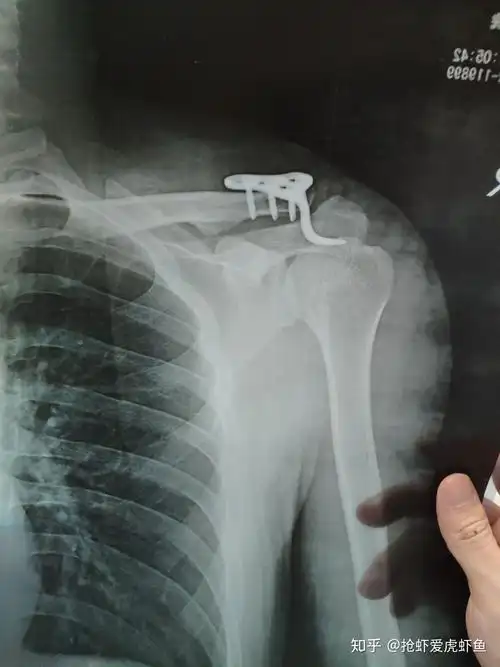

外院锁骨骨折钢板螺钉内固定术后10月

成人锁骨骨折,这样治疗能接受吗